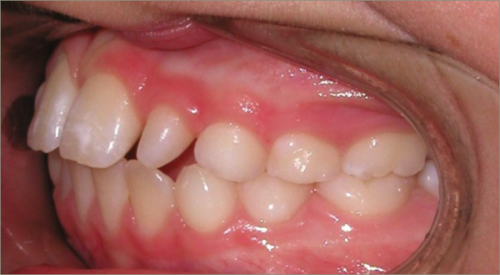

12 year old female:

Diagnosis:

- Missing upper right lateral incisor & lower right cuspid

- Horizontally impacted lower left cuspid

- Peg shaped upper left lateral incisor

Treatment:

- Extraction of impacted lower left cuspid, and peg shaped upper left lateral incisor

- Upper cuspids substituted as laterals

- Full fixed appliances

- 20 months